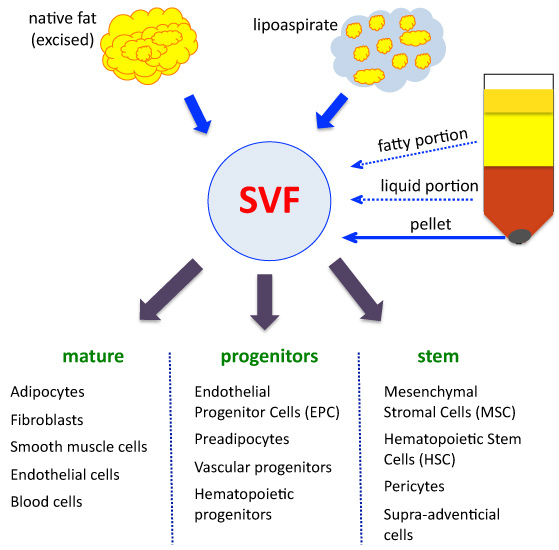

- B. T. Estes, B. O. Diekman, J. M. Gimble, and F. Guilak, “Isolation of adipose-derived stem cells and their induction to a chondrogenic phenotype,” Nature Protocols, vol. 5, no. 7, pp. 1294–1311, 2010. View at Publisher · View at Google Scholar · View at Scopus

- P. A. Zuk, M. Zhu, H. Mizuno et al., “Multilineage cells from human adipose tissue: implications for cell-based therapies,” Tissue Engineering, vol. 7, no. 2, pp. 211–228, 2001. View at Publisher · View at Google Scholar · View at Scopus

- V. Zachar, J. G. Rasmussen, and T. Fink, “Isolation and growth of adipose tissue-derived stem cells,” Methods in Molecular Biology, vol. 698, pp. 37–49, 2011. View at Publisher · View at Google Scholar · View at Scopus